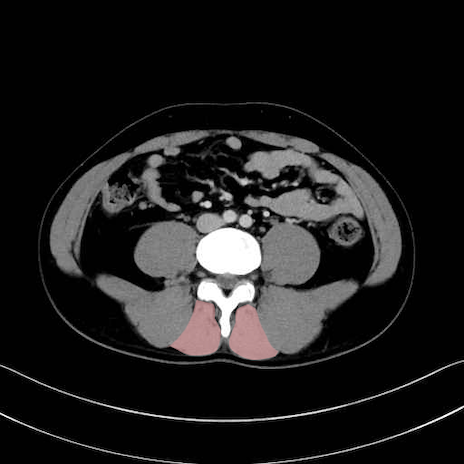

多裂筋 (Multifidus)